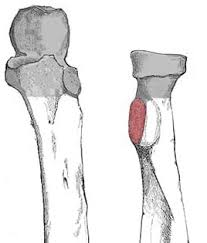

Callus Bone

New bone that forms around fracture during healing.